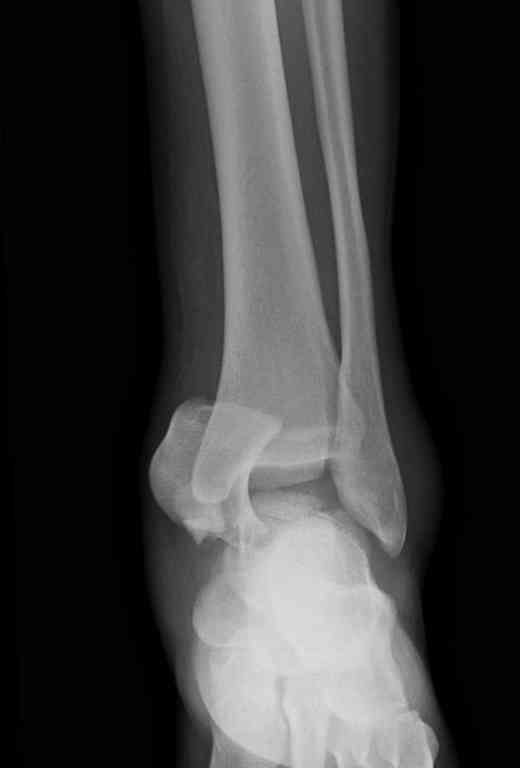

Переломовывих тарана с повреждением медиальной стороны. Через 4 часа после поступления проведена репозиция и фиксация тарана после Irrigation&Debridment. Частичное несращение медиальной лодыжки не беспокоит, вернулся к активному образу жизни. Полная нагрузка разрешена через 11 недель. Финальные снимки через 11 месяцев.